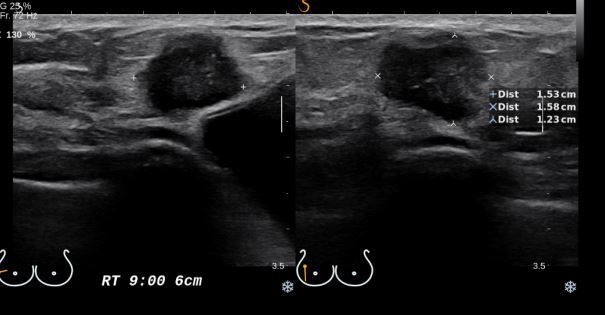

상기환자 우측 유방에 만져지는 멍울로 내원하신 50대 여성 분으로  우측 유방 9시 방향에서 6cm 떨어진 거리의 의심 스러운 혹 조직검사 시행하여 우측 침윤성 유관암 진단 되었습니다.